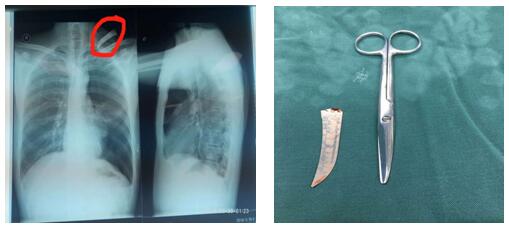

患者左頸根部可見一長約2cm傷口,邊緣整齊,內插入刀片斷端出血不止。左頸根部刀刺傷常常會損傷頸胸部大血管導致大出血危及生命、同時會造成開放性氣胸危及生命,病情非常危急,需行急診開胸探查術。苗主任與李偉主治醫師、李仁栓主治醫師立即制定了手術方案。1:40分患者被送進手術室,在全麻下行胸腔鏡探查楔形切除、肋間血管縫合,胸壁傷口清創術。手術緊張有序地進行。凌晨4點鐘患者安全返回病房,手術順利完成。從患者頸部取出的刀片長約10cm 左右。